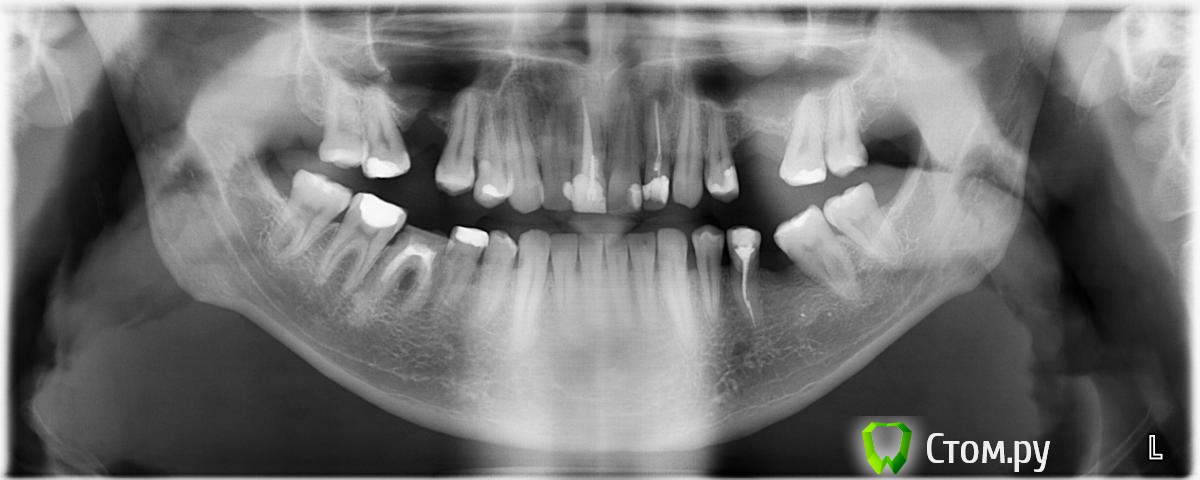

Здравствуйте. В течение ~4-х лет страдаю пародонтитом(диагноз поставлен терапевтом), по ощущениям, увеличена подвижность всех зубов. Многие шейки зубов оголились, часть уже закрыли(где легкий кариес что-то вроде герметика, где поглубже световые пломбы). Хожу на профессиональную чистку, теперь уже раз в 3 месяца. На данный момент ОПТГ выглядит вот так:

да, 6-ку нижнюю сказали на удаление, я в курсе. 2-ку верхнюю лечить буду.